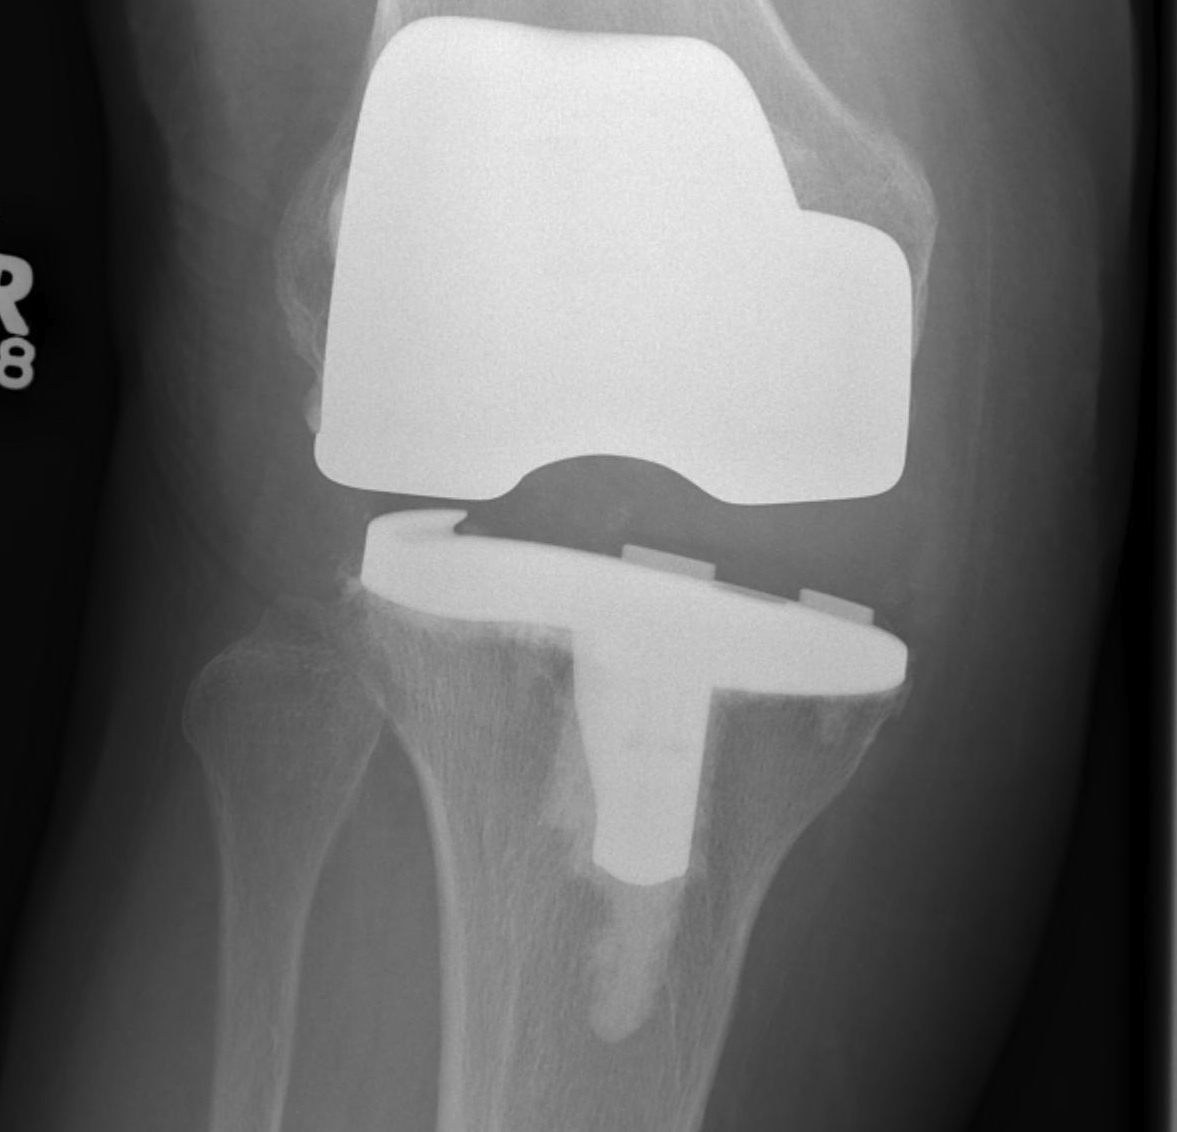

B. Loose in extension

Excessive distal femoral resection

- revise femoral component

- distal femoral augments + stem

B. Loose in flexion and extension

Insufficient poly thickness / wear

- insert larger poly